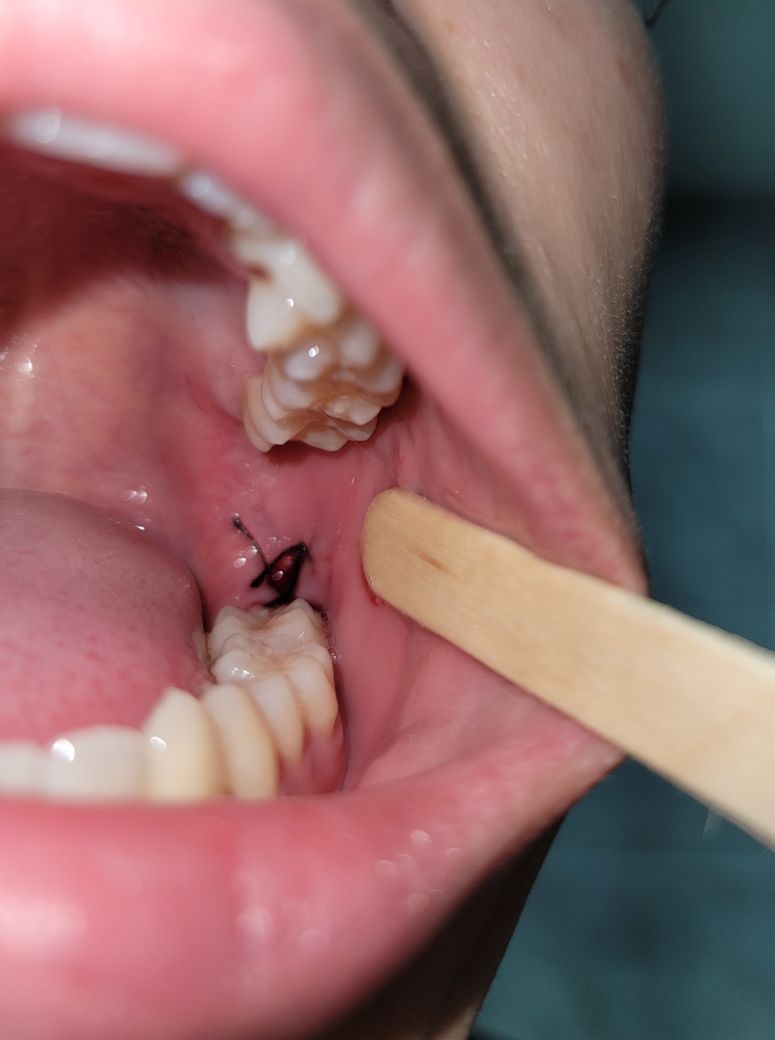

실밥을 한번만 묶었는데 좀 느슨한 느낌이 있고 묶은곳에서 조금 위쪽에는 안 묶인 느낌이라 양 옆으로 절개된 잇몸이 서로 맞닫지 않아 각자 상처가 치유되는 느낌입니다.

반대쪽이랑 비교가 너무 되서 질문합니다.

실밥 묶은 선생님은 다르셨어요.

• 2번 째 사진

완전히 닫히도록 매듭이 지어지지 않습니다. 현재 사진상 잘 낫고 있는 것으로 확인이 됩니다.

사진상으로 크게 문제가 있어 보이진 않습니다. 잇몸이 부어 잇는 상태에서 실밥을 꿰메고 나서 붓기가 빠지면 약간 느슨해 질수도 있습니다.